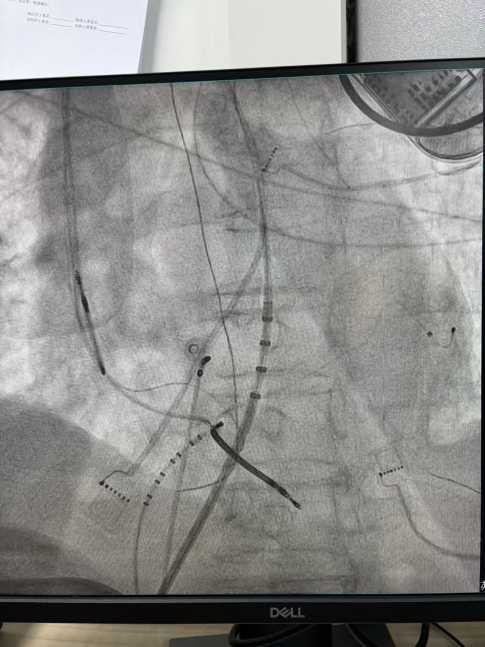

干穿心包进入外膜标测

心外膜基质

部分内膜室速靶点电位

王林林主任医师谨慎操作,成功进入心外膜达到病变位置。术中,患者反复自发多形态室速,且转为室扑,同时出现血流动力学不稳定,需多次电除颤方能终止发作,标测难度极大。这就要求医疗团队必须在有限的标测时间内精准定位室速消融靶点,并结合心内外膜基质特征制定消融策略。经针对性消融后,患者未再自发室速,且室性早搏转为单一形态,经判定为右心室乳头肌来源,随即予以一并消融。术后经心室程序电刺激验证,室速未再被诱发。

右心室后组乳头肌室早电位